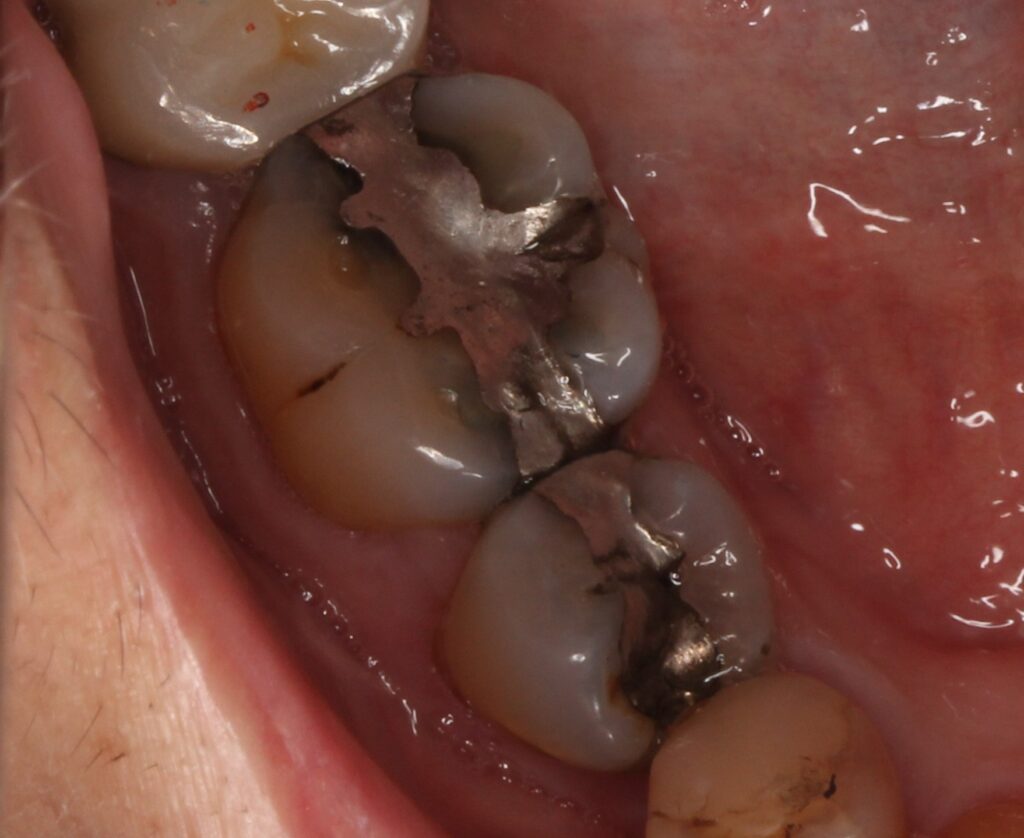

虫歯で溶けて、歯の大部分が崩壊している状態です。どんどんと歯の中に細菌が入り込んで感染が広がっています。歯の根の先に膿が溜まってくると、歯ぐきが腫れを繰り返します。

治療方法は抜歯となります。歯を抜いた後は、入れ歯、ブリッジ、インプラントなど歯を入れる処置が必要です。